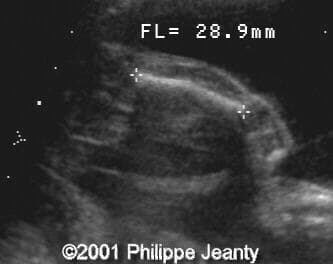

This fetus has a small amount of bowing and shortening of the right leg (compare to the left leg on the second image):

image19

image20